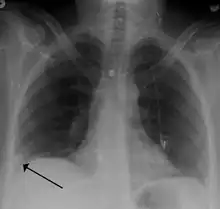

Pulmonary embolism (white arrow) that has been long-standing and has caused a lung infarction (black arrow) seen as a reverse halo sign.

- Chest X-rays are often done on people with shortness of breath to help rule-out other causes, such as congestive heart failure and rib fracture. Chest X-rays in PE are rarely normal,[68] but usually lack signs that suggest the diagnosis of PE (for example, Westermark sign, Hampton's hump).